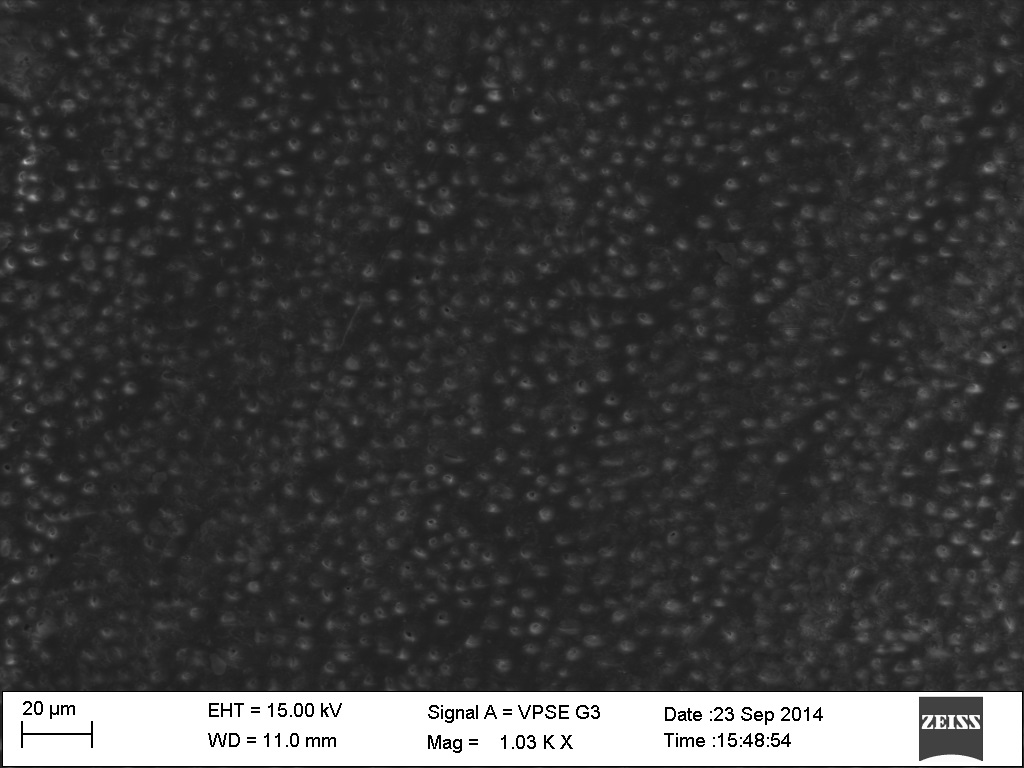

Fig. 1: It shows an SEM image of the dentinal tubules and smear layer removal viewed after irrigation with Neem at 1000x magnification

Of the alternative irrigants used Amla (1.38±0.07) (fig. 3) showed the best results. There was no significant difference in the smear layer removing ability of NaOCl+EDTA and Amla. This was followed by Neem (1.7±0.13) (fig. 1) and Triphala (2.08±0.05) (fig. 2).

Fig. 2: It shows an SEM image of the dentinal tubules and smear layer removal viewed after irrigation with Triphala at 1000x magnification

There was a significant difference between the efficacy of Amla and Neem/Triphala (p<0.05). There was a significant difference between the efficacy of Neem and Triphala (p<0.05).

Fig. 3: It shows an SEM image of the dentinal tubules and smear layer removal viewed after irrigation with Amla at 1000x magnification

Fig. 4: It shows an SEM image of the dentinal tubules and smear layer removal viewed after irrigation with EDTA at 1000x magnification

Fig. 5: It shows an SEM image of the dentinal tubules and smear layer removal viewed after irrigation with saline at 1000x magnification